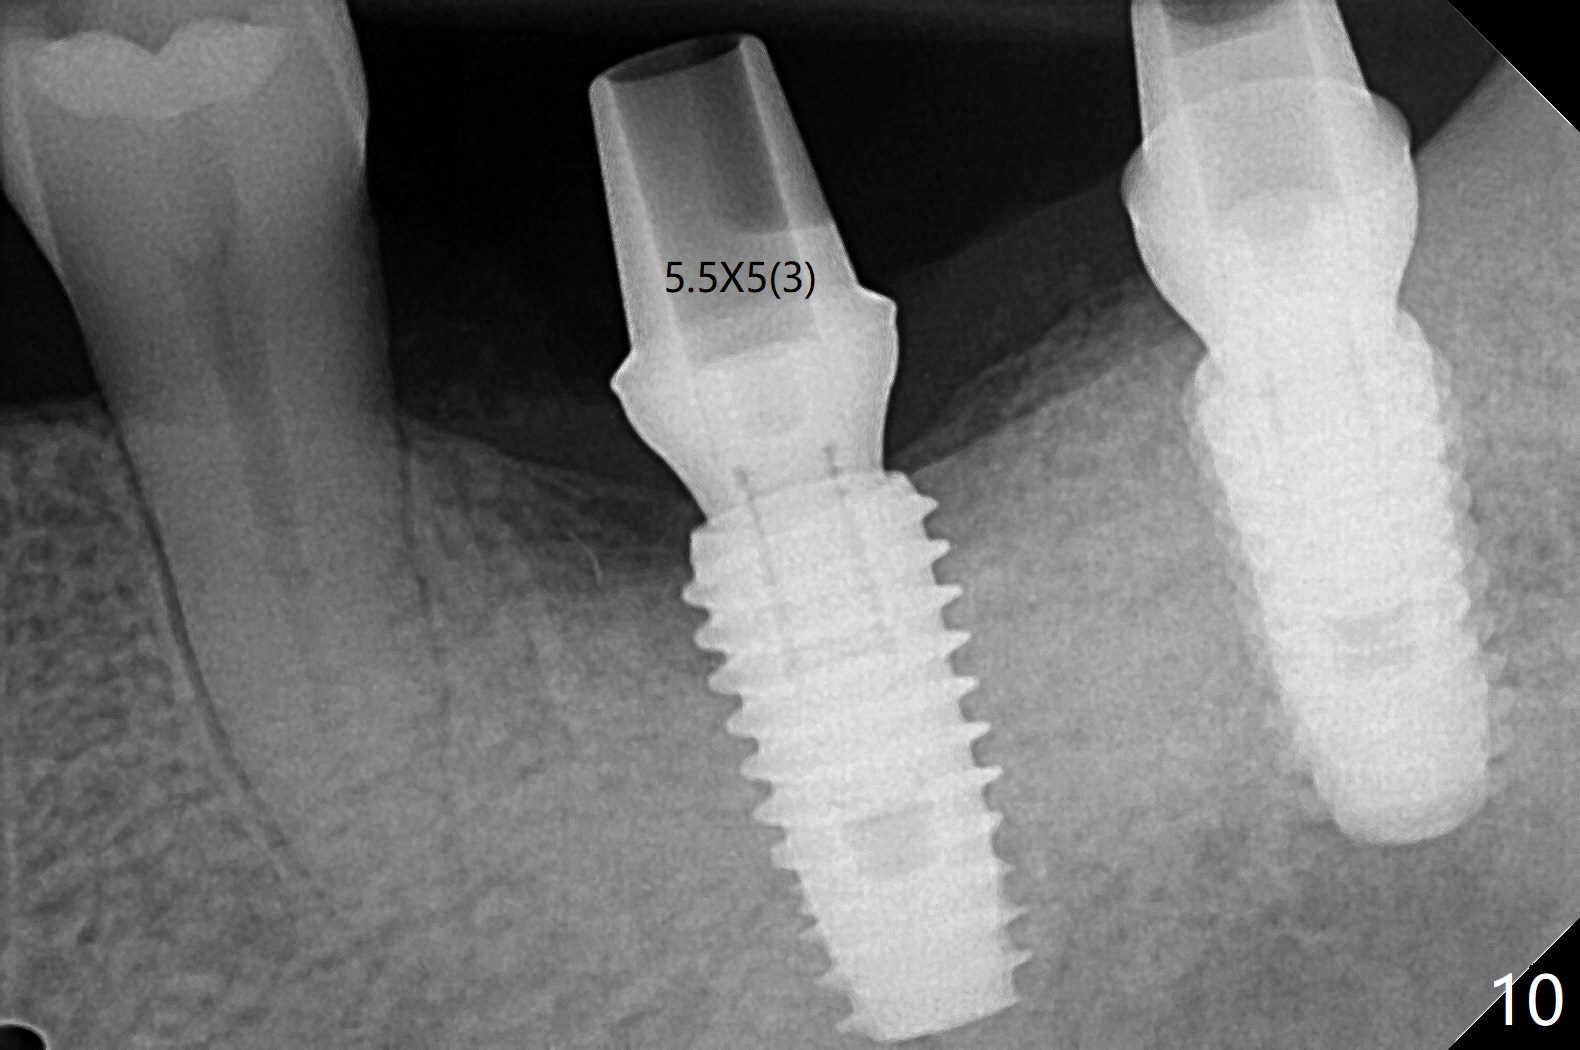

After finishing osteotomy with guide, a 5x14 mm tissue-level implant tap is used without guide because of limited mouth opening. It is not parallel to the implant at #19 (Fig.1). A bone-level implant is barely able to be placed with guide; it is parallel to #19 implant (Fig.2). Pre- and intra-op exam confirms periimplantitis at #19. In addition the horizontally impacted #17 has caries. A large incision is made for #19 debridement and bone graft. #18 bone graft (Fig.2 *) and #17 extraction and Osteogen plug (O) placement. Postop CT shows poor trajectory of #19 implant (Fig.3 (coronal section) free hand placement), which is associated with screw loosening and periimplantitis (lingual (L) threads supracrestal). In contrast #18 implant has good trajectory and placement level (Fig.4). The mesial defect of #19 seems to have been repaired and the implant at #18 osteointegrates 7.5 months postop (Fig.5). The wound at #19 heals except a small slit 7.5 months postop (bone graft, Fig.6). When the incompletely seated healing screw (Fig.2,3) is removed during uncover, it is difficult to place a cemented abutment. A healing abutment is placed instead. In fact the hex of the abutment fractures within the implant well (Fig.7,8 < (due to burial of 1.2 driver inside the abutment and bruxism)). Because of the deeply placed implant, incision is made and surgical long fissure bur is used to section the lingual (Fig.9 L) portion of the hex. When the buccal (B) portion of the hex is being sectioned, the hex dislodges by itself. There is no problem to insert a cemented abutment (Fig.10). Later a longer cuffed abutment is placed and bone graft is placed around the coronal threads (Fig.11 *). The bone graft around #19 implant looks stable 2 weeks post 2nd grafting (Fig.12). Return to Prevent Molar Periimplantitis (Protocols, Table) No Deviation Screw Xin Wei, DDS, PhD, MS 1st edition 02/10/2020, last revision 02/26/2021